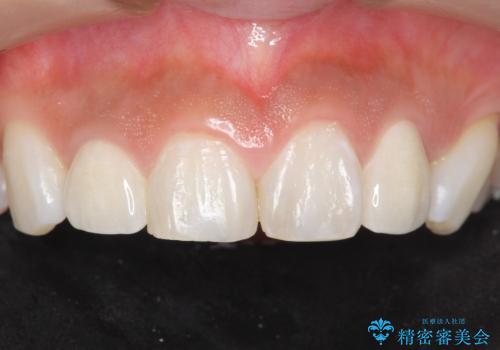

- 上の前歯の色と隙間を気にされ、来院された患者様です。

精査したところ、右上の側切歯(右上2)は神経が死んで変色しており、左上の側切歯と犬歯の間に2mm程度の隙間を認めました。

矯正せずに早く治したいという強いご希望により、セラミッククラウンによる補綴治療(上顎両側2の2本)を行いました。

天然歯のような自然な仕上がりに大変喜んで頂けました。

クラウンの種類:オールセラミッククラウン スペシャル